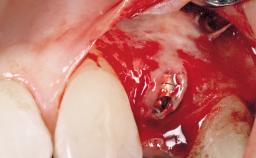

A 39-year-old male patient presented with a chief complaint of discomfort and gingival discoloration around his maxillary left central incisor. He was in good general health and was a non-smoker. His past dental history was significant because of the traumatic fracture of tooth 21 in a sporting accident at age 13. Initial dental treatment included endodontic therapy and a full-coverage restoration. The patient became symptomatic 5 years later, when structural failure of the tooth resulted in the dislodgment of the crown. Endodontic retreatment, apical surgery, and post-and-core restoration were performed.

Type of Implants One-Piece

Attachment One-Piece

Bone Augmentation Horizontal|Staged

Augmentation Materials Xenogenous|Membrane

Bone Volume Deficient horizontally, requiring prior grafting